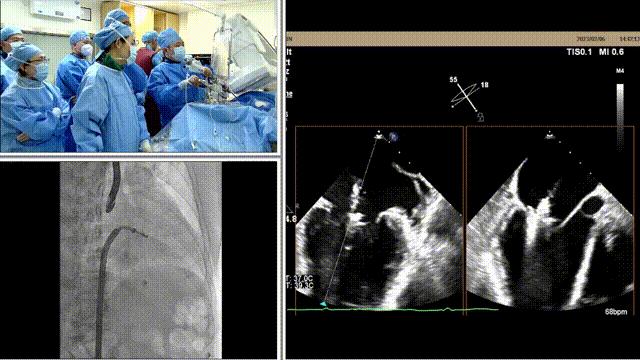

在经食道超声及DSA辅助下,术者通过反复评估二尖瓣反流位置、抓捕位置、反流程度,巧妙夹合,在2区植入1枚DragonFly™夹子。患者术后反流程度从3+转至接近零反流,手术取得圆满成功。

瓣叶捕获

关闭瓣膜夹后评估